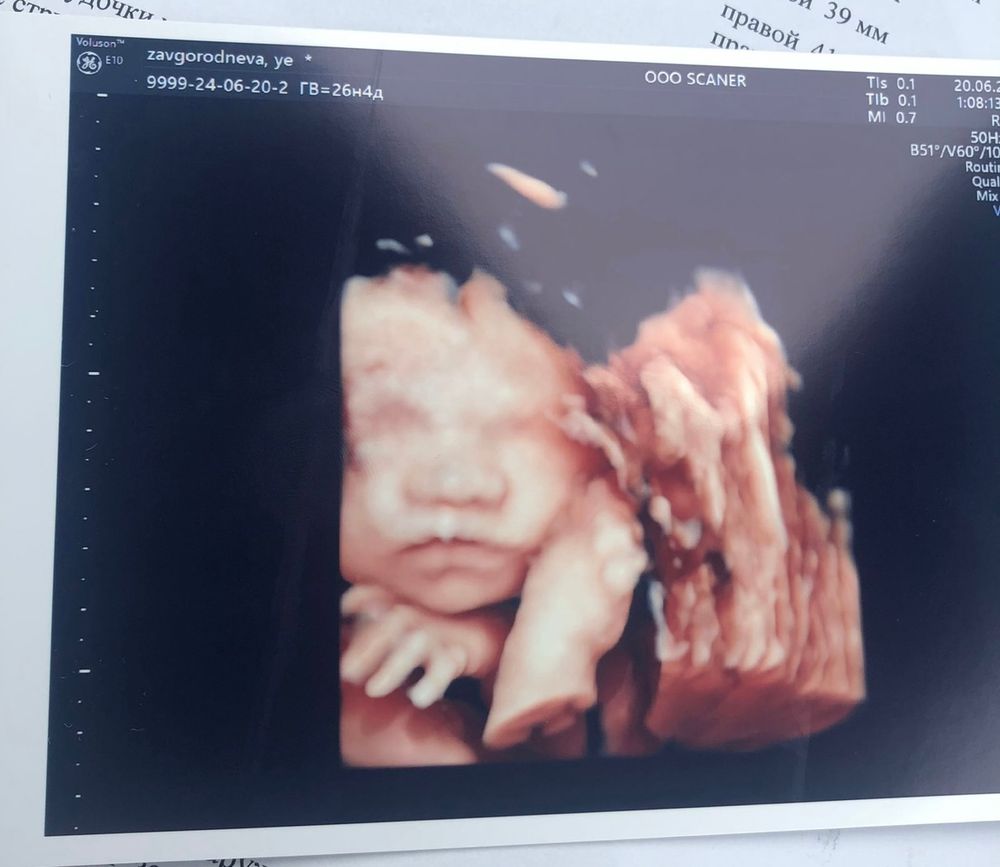

Momo

26 недель)

Но кадр мы словили только спустя 30 минут и один единственный